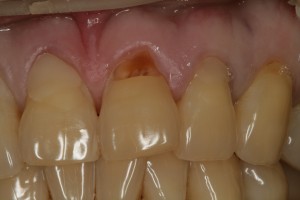

왼쪽 위 중절치가 많이 패였다며 내원하신 환자분의 임상사진입니다.

치아와 잇몸사이 부분인 치경부가 많이 패여있음을 볼 수 있습니다. 이것을 치경부 마모증이라고 합니다.

과도한 교합력, 잘못된 칫솔질 등의 원인으로 치경부 마모증이 생기게 됩니다.